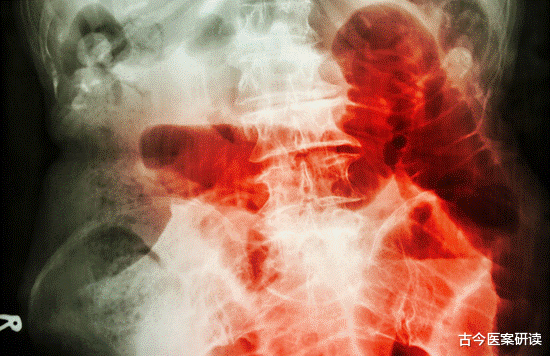

- 肠镜|肠镜选无痛好还是普通好?二者有何区别?不妨听听医生的分析!